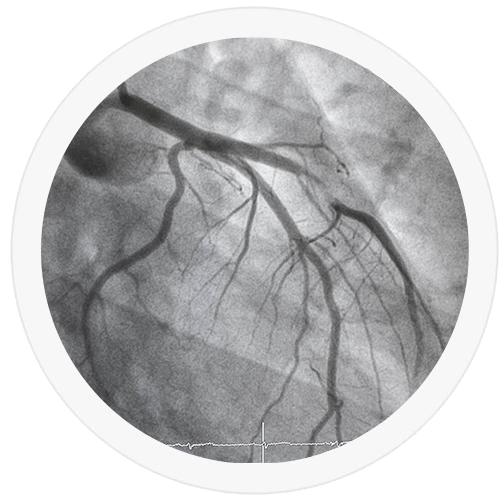

Coronarographie

Une coronarographie est un examen utilisant les rayons X pour permettre, au moyen d’un produit de contraste, une visualisation précise des artères coronaires qui irriguent le muscle cardiaque en sang. Il s’agit d’un examen qualifié d’invasif puisqu’il nécessite de ponctionner une artère au niveau du poignet ou, plus rarement, au niveau de l’aine. L’objectif de cet examen est de rechercher, voire de traiter, un « encrassement » (athérome) des artères coronaires.

Après avoir été accueilli dans le service de cardiologie où un point sera fait sur votre dossier, vous serez transporté en salle de cathétérisme pour la réalisation de l’examen. Celui-ci débute par la réalisation d’une anesthésie locale au niveau du point de ponction, puis un cathéter est introduit dans une artère, permettant son cheminement jusqu’aux artères coronaires. Une fois le cathéter en place, un produit de contraste sera injecté, et des acquisitions radiographiques seront réalisées permettant d’analyser les artères sur l’ensemble de leur trajet. Si un geste d’angioplastie est nécessaire, il pourra être réalisé dans la continuité de cet examen, permettant l’implantation d’autant de stents que jugé nécessaire par le médecin coronarographiste.